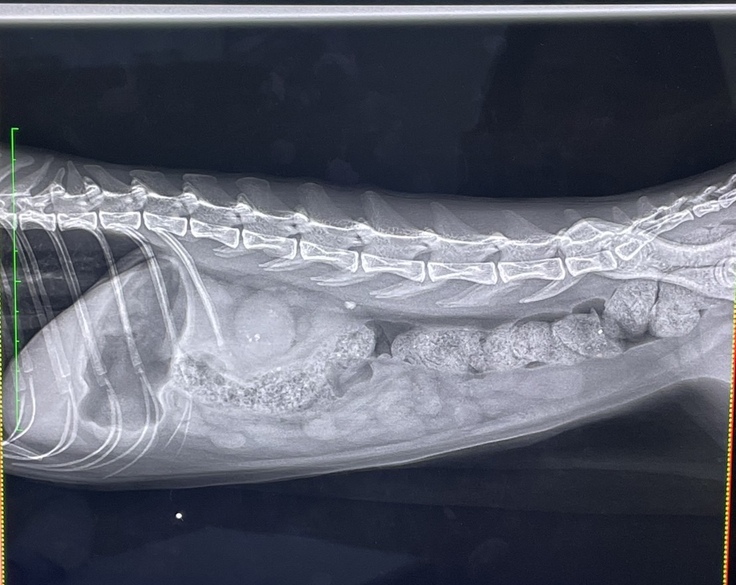

点滴入院を続けても、みしぇるの状態は悪化するばかりで数値の改善も見られず、大学病院(後B病院)を紹介していただき、3/4に受診しました。その結果、腎臓・尿管ともに結石が見られ、尿管は結石により詰まっており、腎臓も圧迫されている状態でした。

直ちに入院、手術が必要であると判断され、3/4受診日当日に、一つ目の手術を行いました。腎臓に直接カテーテルを挿入し、チューブから直接排尿できるようにしてもらいました。

3/7、術後の経過は良く、クレアチニンの数値も下がりつつあったため、2つめの手術を行いました。右側の尿管は切開して結石を取り、左側の尿管は閉塞部が膀胱に近かっため、尿管を一度膀胱から切り離して新たにつなげなおす手術を行いました。